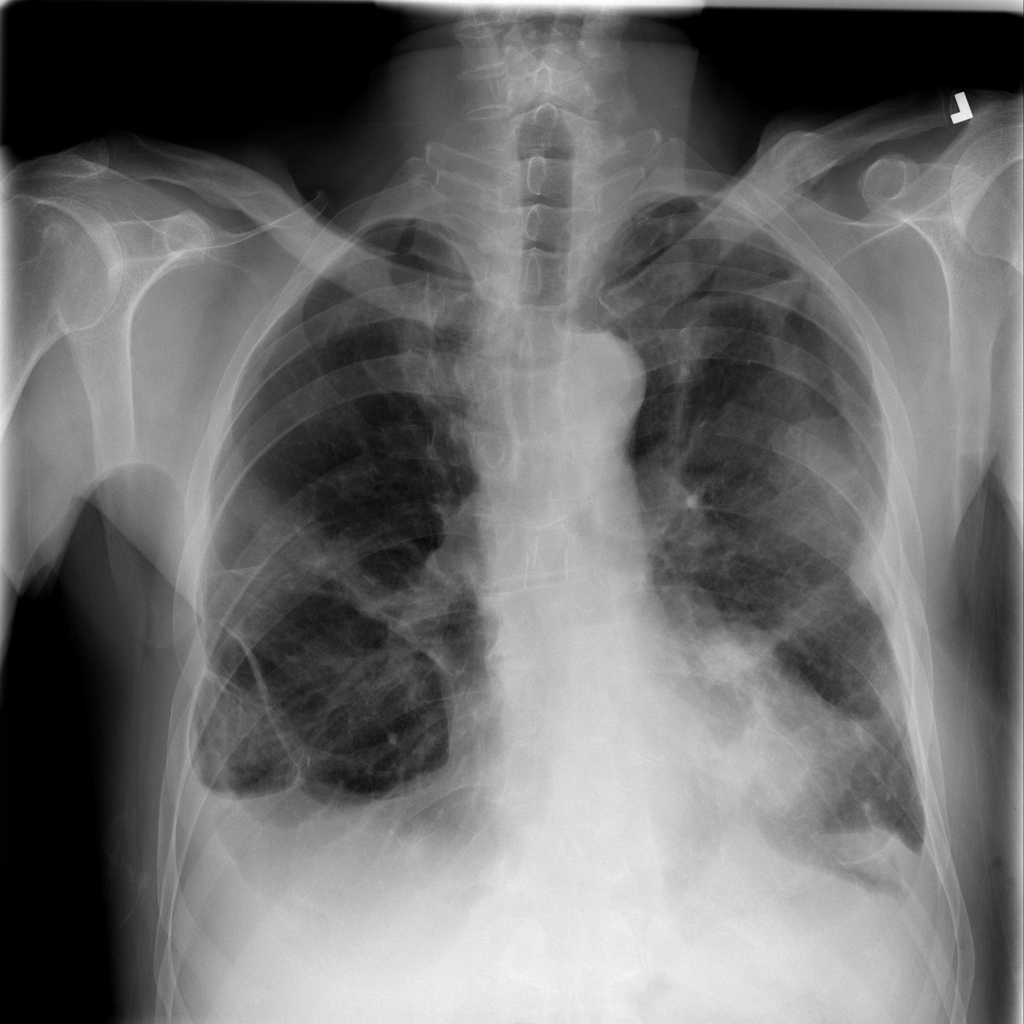

PAT-E81B · IMG-000Effusion

PAT-E81B · IMG-000

PA